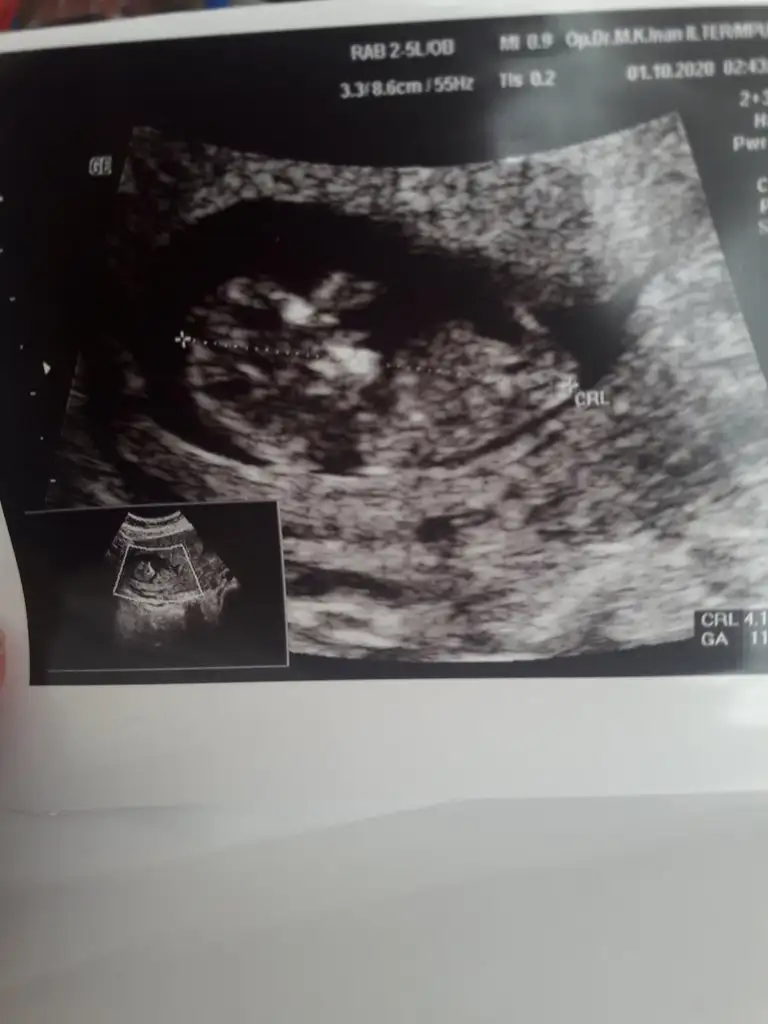

Sanki sanki diyerek kız gibi gibi tekrar USG paylasinBana da yorum yapabilir misiniz @İkra meyra. Ultrason cihazı biraz kötüydü ama 11 haftalık

Sanki erkek tekrar USG paylasinBana da yorum yapabilir misiniz @İkra meyra. Ultrason cihazı biraz kötüydü ama 11 haftalık

Kaç haftalık büyük sanki USG 11 12 13 haftalar olmalı sanki sanki kız gibi tekrar USG paylasinBana da tahminde bulunabilir misiniz acaba